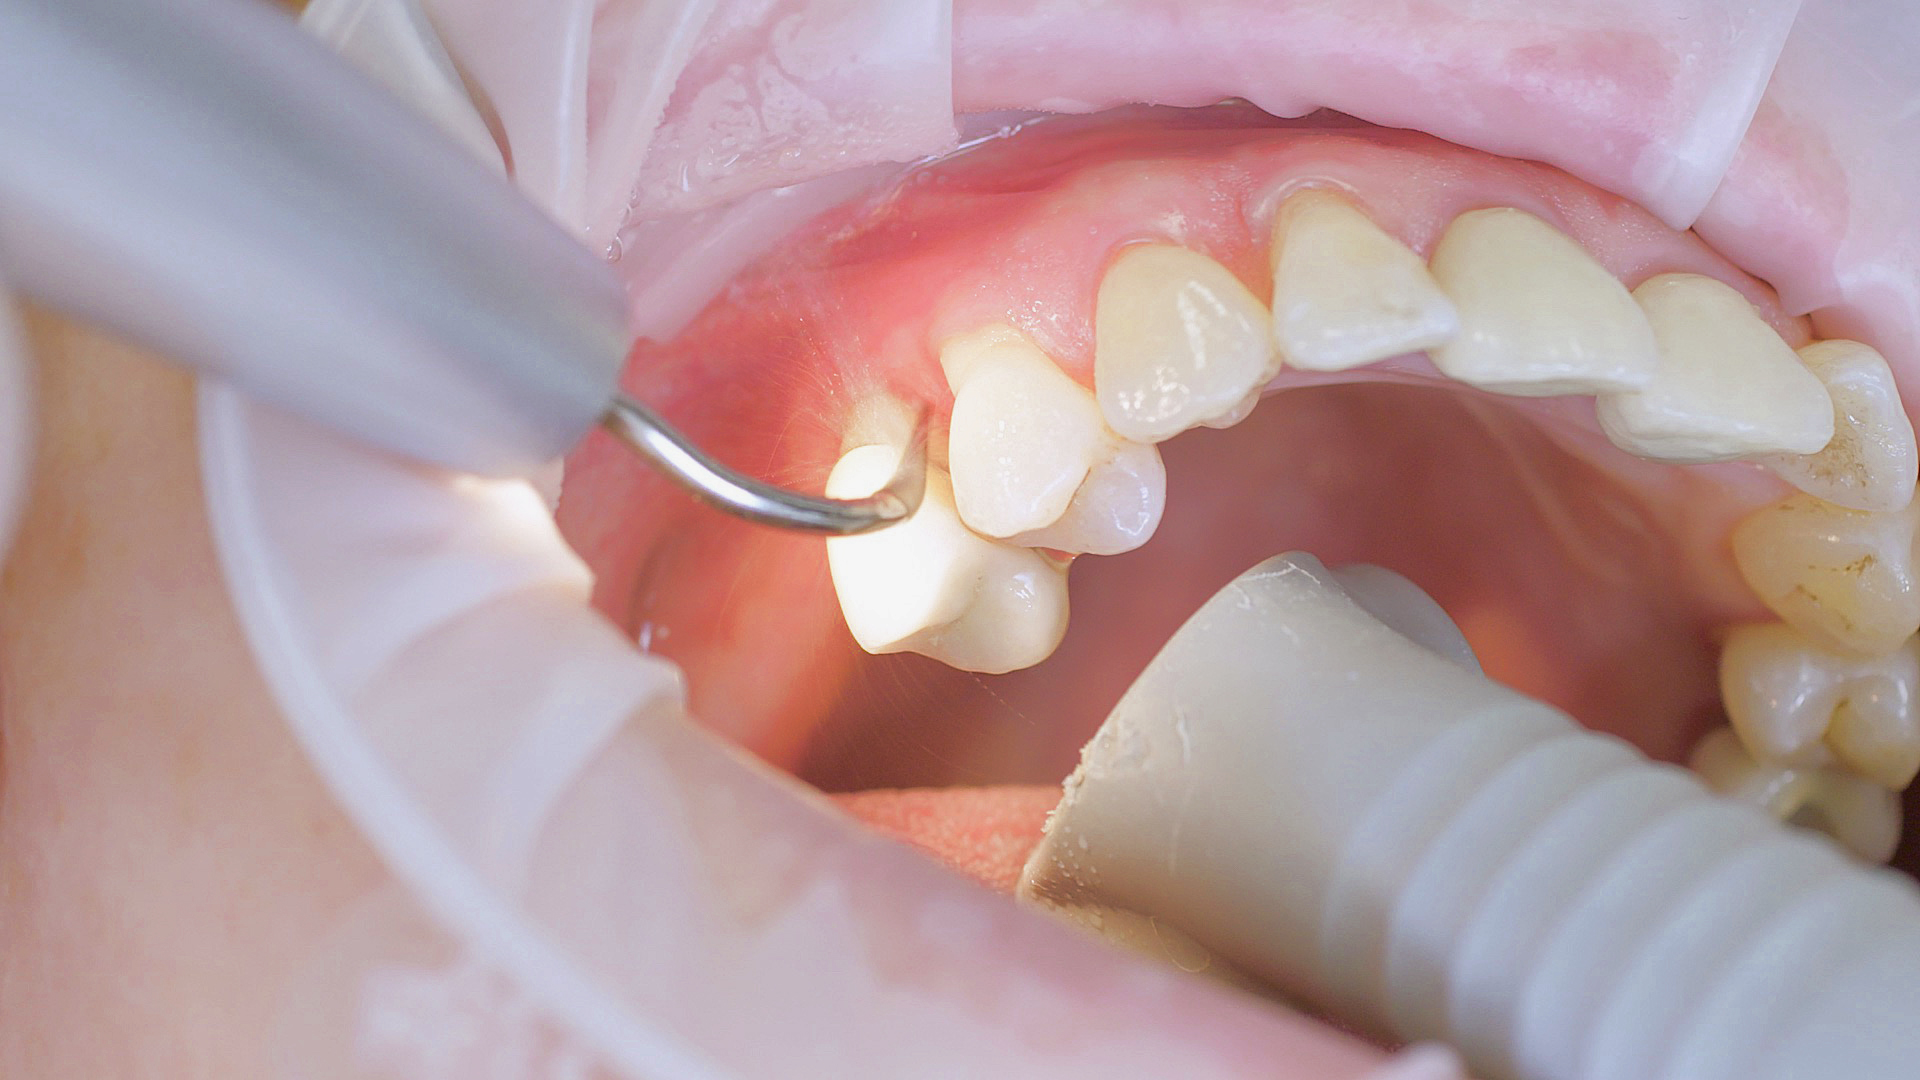

Every dental examination is based on a detailed medical history combined with targeted diagnostics con- taining as much detail as possible: The dentist records systemic risk factors such as diabetes or smoking and identifies any potential increased tendency to inflammation.[3] Hard and soft tissues are examined and periodontal pockets are probed in a screening test according to PSR (Periodontal Screening and Recording). In case of abnormal findings, the periodontal status is then re- corded and therapy is initiated where necessary. This treatment begins with professional biofilm management, by using, for example, rotary cups and polishing com pounds (Fig. 1), and comprehensive instructions in oral hygiene. Sonic or ultrasonic systems remain an effective alternative or supplement to manual instruments for sub- gingival debridement and biofilm management (presentation by Prof. Dr Ulrich Schlagenhauf; Fig. 2). Supplementary use of photodynamic therapy, air polishing or local and systemic antibiotics is not adequately documented (Prof. Dr Sema Hakki).[4] According to Dr Sergio Bizzarro, improved biomarker diagnostics may lead to an increase in customised patient therapy in the future.

Good individual oral hygiene and professional biofilm management

Fig. 1: Good individual oral hygiene and professional biofilm management, e.g. with cups and brushes, helps support periodontal and peri-implant health.